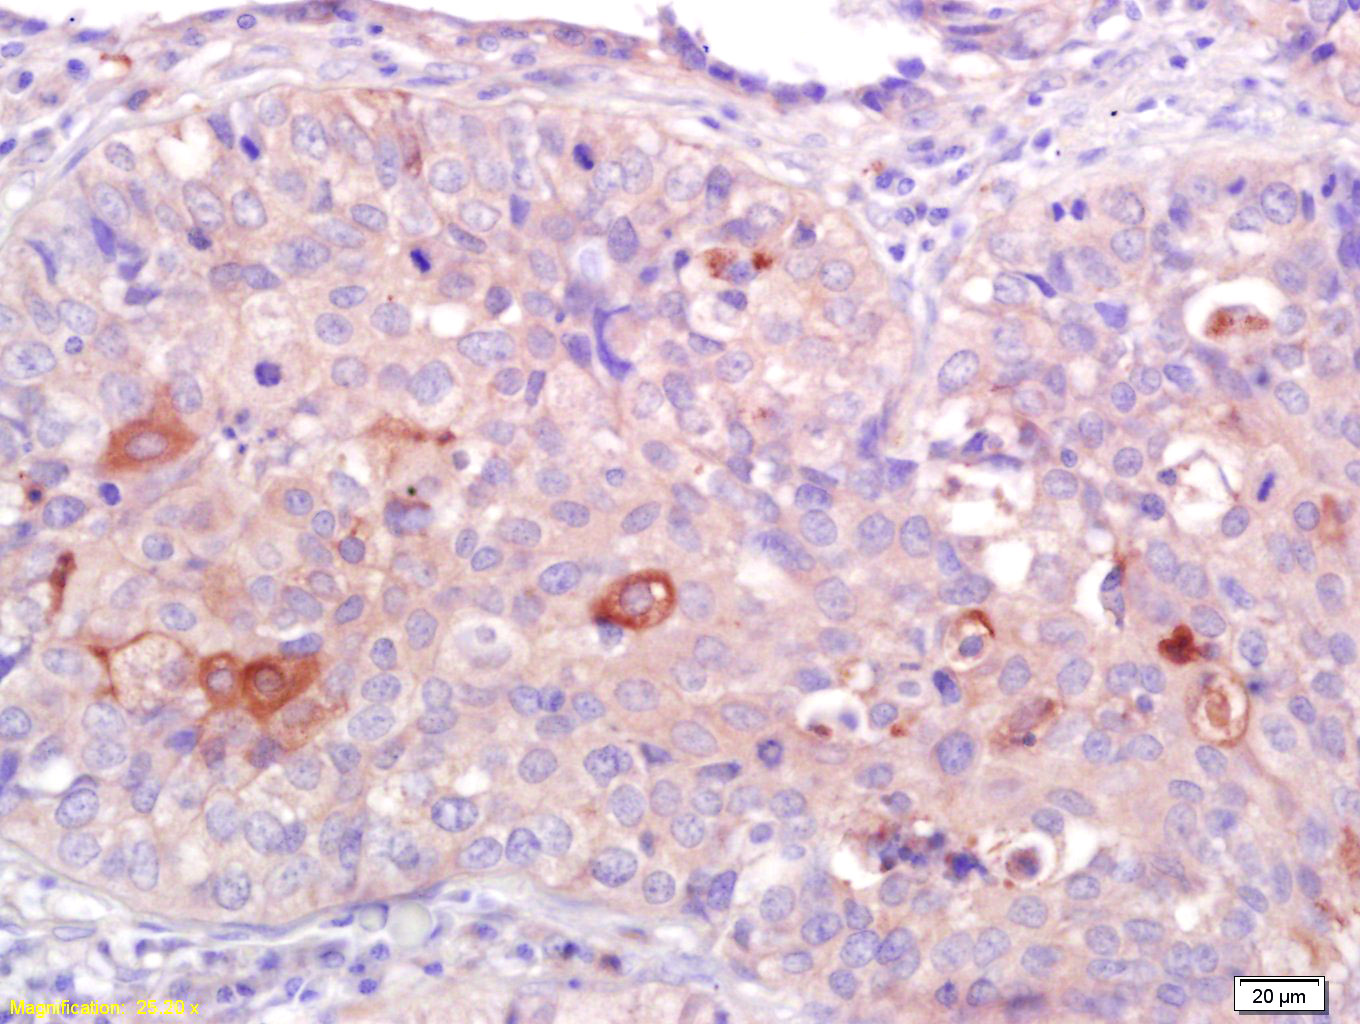

Tissue/cell: human lung carcinoma; 4% Paraformaldehyde-fixed and paraffin-embedded; Antigen retrieval: citrate buffer ( 0.01M, pH 6.0 ), Boiling bathing for 15min; Block endogenous peroxidase by 3% Hydrogen peroxide for 30min; Blocking buffer (normal goat serum,C-0005) at 37℃ for 20 min; Incubation: Anti-CNR2/CB2 Polyclonal Antibody, Unconjugated(bs-2377R) 1:200, overnight at 4°C, followed by conjugation to the secondary antibody(SP-0023) and DAB(C-0010) staining